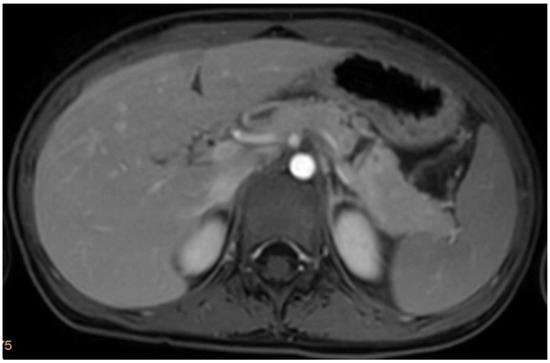

| Initial diagnosis obtained by | Computed Tomography | Computed Tomography | Magnetic Resonance Tomography | Computed Tomography |

| Initial Management | Laparotomy, suture of the pancreatic head, distal pancreato-jejunostomy (Roux Y) | ERCP—complete dissection of the pancreas, Laparotomy, Jejunal repair, suture of the pancreatic head, distal pancreato-gastrostomy | ERCP—stenting of the ruptured pancreatic duct with 5 Ch pigtail drainage | ERCP unsuccessful, stenting of ruptured pancreatic duct not possible; chest drain (left side) |

| Postoperative Complications | Portal vein thrombosis with partial obstruction | None | Symptomatic pancreatic pseudocyst infection with Clostridium difficile | Symptomatic pancreatic pseudocyst Candida albicans sepsis; Posttraumatic stress disorder |